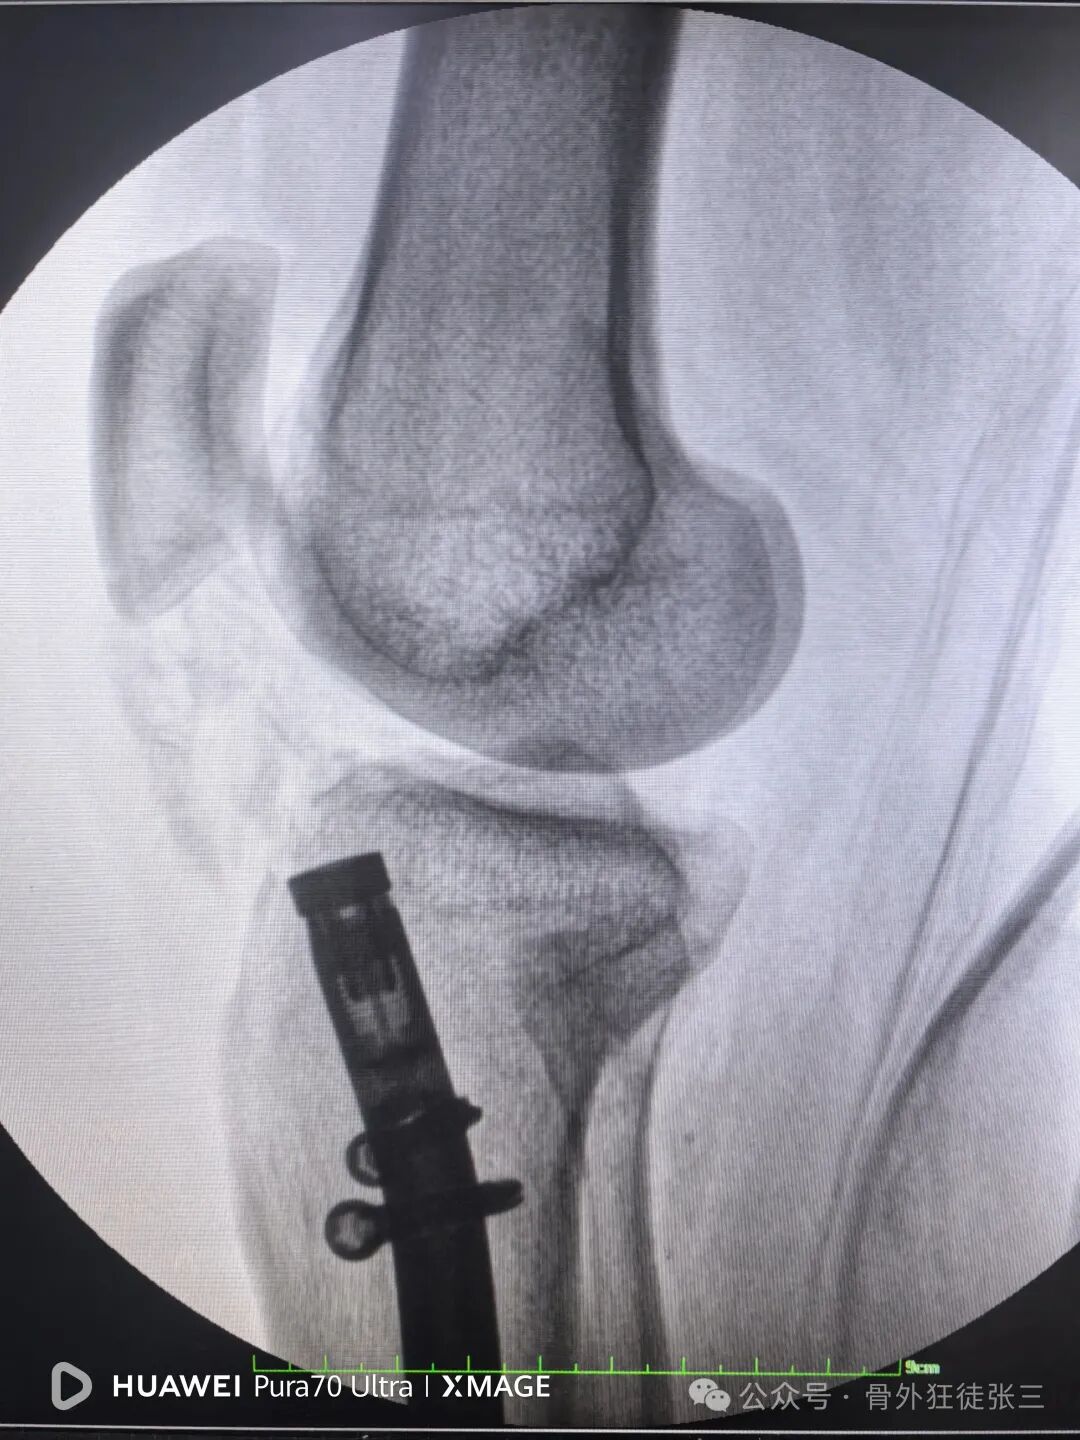

近年来,髌旁外侧入路髓内钉技术因复位精准、创伤小、康复快等特点,得到了广泛的应用。本文将围绕一例胫腓骨骨折案例,详细介绍该手术过程,为临床同仁提供思路与参考。

胫腓骨骨折

如何避免进针点偏外的处理

就能顺利纠正